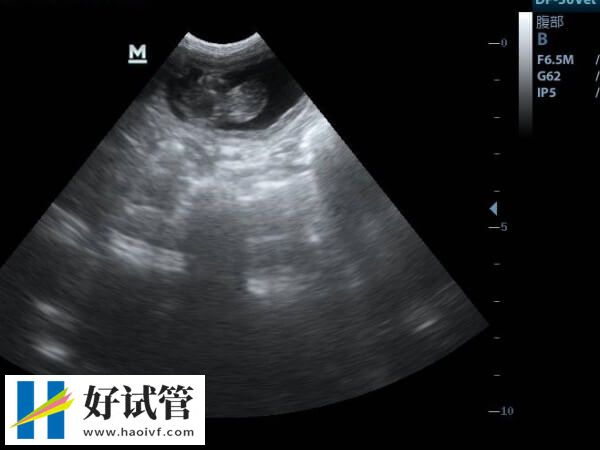

2、药物促卵及卵泡监测费用

在香港大学深圳医院进入到试管周期后,女方需要使用促排药物,由于个体的差异,每一个治疗者使用的药物剂量和使用药物的时间都不一样,这也就导致不同女性之间的促排费用差异化,通常情况下是年龄大的女性这一部分的花费相对要高一些,通常在10000-30000元左右。